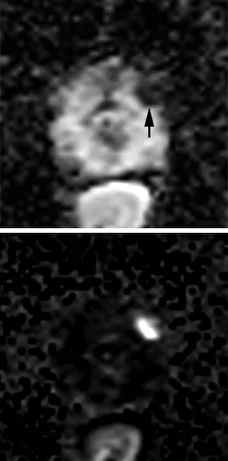

Peripheral Zone (PZ)

Нет раннего накопления контрастного препарата, или диффузное мультифокальное накопление, не соответствующее очагу на Т2 и DWI

Раннее накопление контрастного препарата (раньше или одновременно с нормальной тканью железы), соответствует очагу на Т2 и DWI